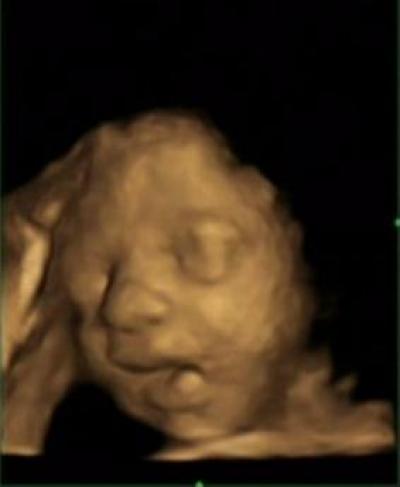

My baby wouldnt open its hands in my ultrasound. Ultrasound linear transducer is placed parallel to the lateral aspect of the infants hip. Fetal clenched hands are an antenatal ultrasound observation where the fetal hands are in a constant permanently clenched position as if being unable to extend.

If your baby is sleeping during the appointment you wont. In this prospective study 100 second trimester fetuses were assessed to determine the frequency of visualization of the open fetal hands and the three phalanges of the fifth digit during a routine ultrasound examination. That is the first question a coworker asked my husband when he returned to work following our 20-week anatomy scan.

The next ultrasound last week hand where wide open and the other marker disappeared. The ultrasound technician will be looking for physical abnormalities on the baby checking the location of the placenta and measuring your babys growth. A prospective type 1 cohort study was conducted in a tertiary prenatal.

Ten fingers ten toes. Pathology Some authors 3 suggest that the abnormal posture results in part from.